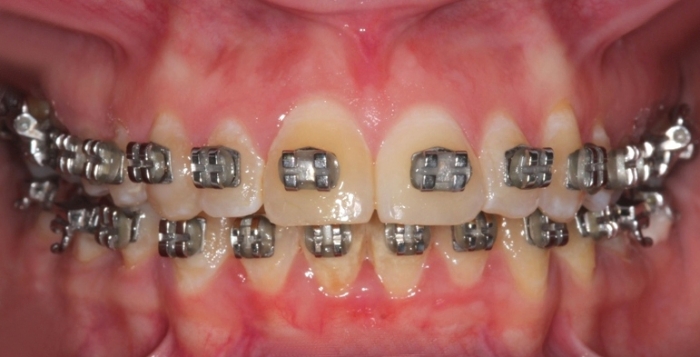

Mordida após a cirurgia